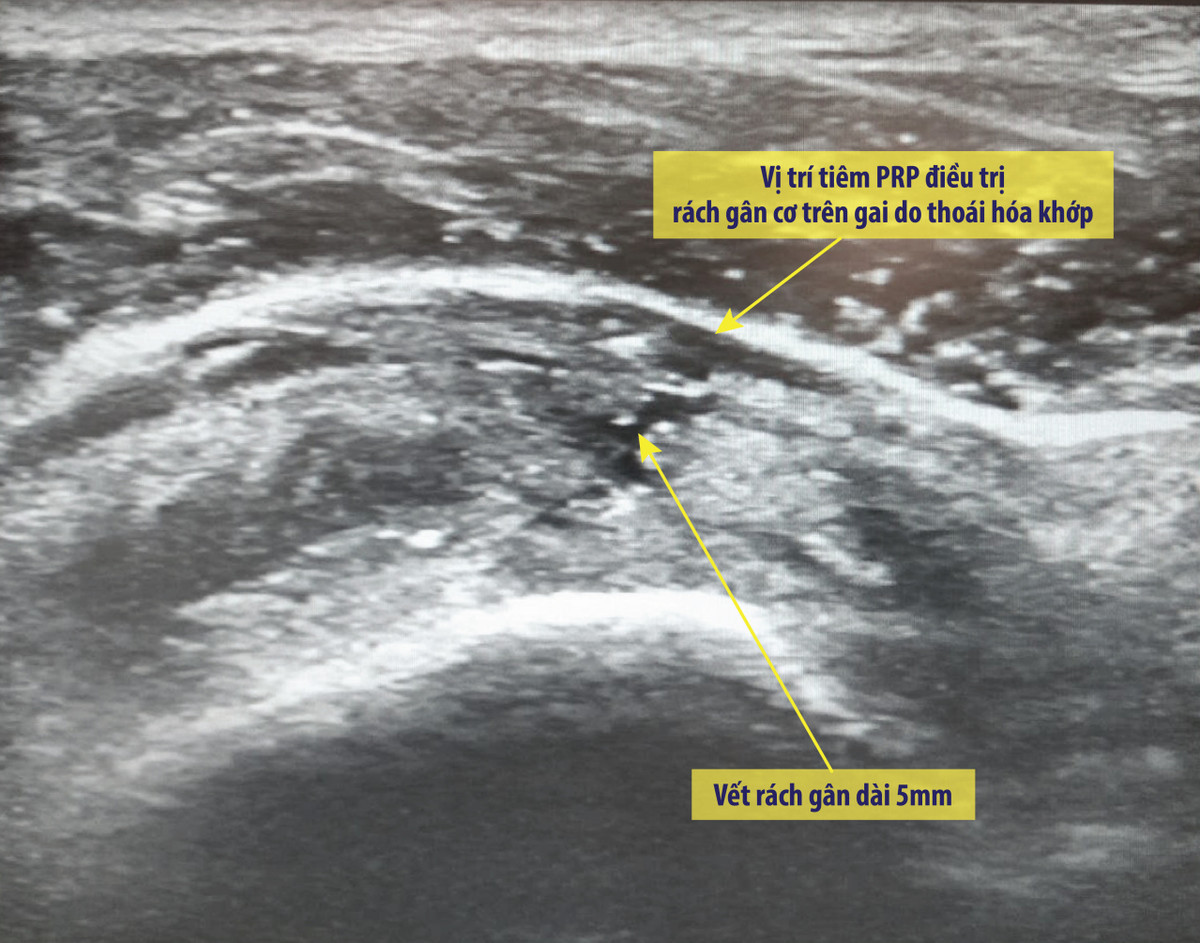

Điểm đặc biệt là các ca tiêm PRP điều trị viêm khớp tại Bệnh viện Vinmec đều diễn ra dưới hướng dẫn của máy siêu âm để xác định trúng vị trí cần tiêm.

Theo BS Nhung cho biết: “Tiêm chế phẩm PRP nhằm tác động trực tiếp vào tổn thương nên việc xác định đúng vị trí cần tiêm là rất quan trọng. Dưới hướng dẫn của máy siêu âm GE Healthcare S9 hiện đại có đầu dò phẳng, tần số cao, độ phân giải HD cho hình ảnh rõ nét, êkip gồm bác sĩ cơ xương khớp và bác sĩ chẩn đoán hình ảnh có thể tìm được vị trí chính xác gây thoái hóa khớp vai và tiêm trực tiếp vào vị trí đó”.

Việc tiêm PRP dưới hướng dẫn siêu âm có khả năng tạo sự khác biệt trong hiệu quả điều trị nhờ tác động trực tiếp và chính xác vào vị trí tổn thương.